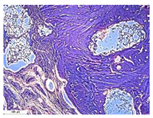

| Point | Type of Microscopy | ||||

|---|---|---|---|---|---|

| Standard Light | Standard Light | Polarization | Standard Light | Phase Contrast | |

| Staining with Hematoxylin–Eosin | Staining with Picrosirius Red | Staining with Picrosirius Red | Staining with Hematoxylin–Eosin | Staining with Hematoxylin–Eosin | |

| 3 | ![]() | ![]() | ![]() | ![]() | ![]() |

| 5 | ![]() | ![]() | ![]() | ![]() | ![]() |

| 8 | ![]() | ![]() | ![]() | ![]() | ![]() |